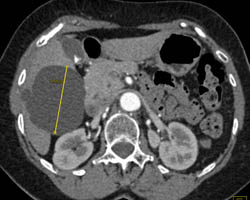

Cholangiocarcinoma of the Distal Common Bile Duct (CBD) Which Is Enhancing- See Full Sequence